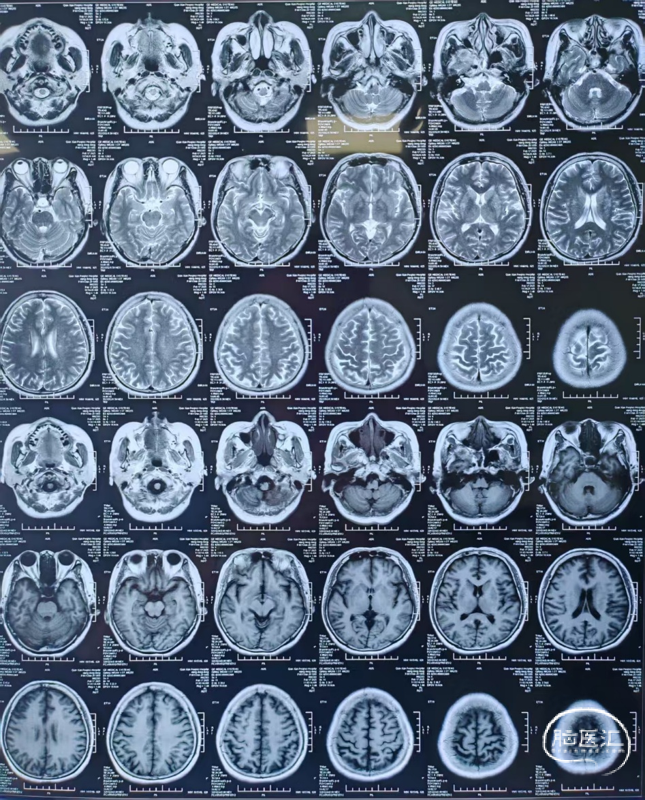

颅脑MRI+MRA